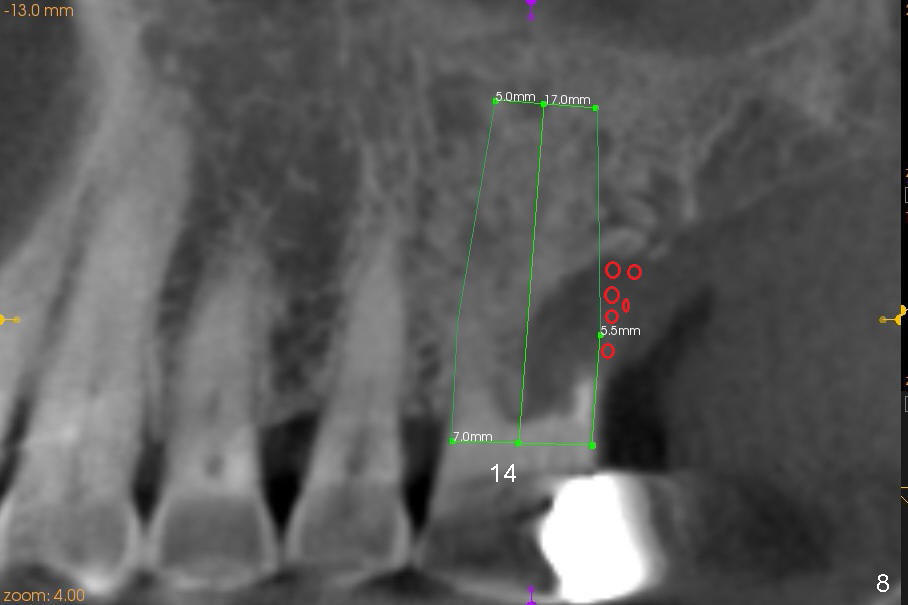

The tooth #14 is periodontally compromised with supraeruption (Fig.8-10). After immediate implant, bone graft (red circles) is needed distally (Fig.8) and palatally (Fig.9).